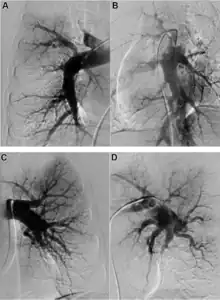

Early diagnosis still remains a challenge in CTEPH, with a median time of 14 months between symptom onset and diagnosis in expert centres.[7] A suspicion of PH is often raised by echocardiography, but an invasive right heart catheterisation is required to confirm it.[6] Once PH is diagnosed, the presence of thromboembolic disease requires imaging. The recommended diagnostic algorithm stresses the importance of initial investigation using an echocardiogram and V/Q scan and confirmation with right heart catheter and pulmonary angiography (PA).[8]

Both V/Q scanning and modern multidetector CT angiography (CTPA) may be accurate methods for the detection of CTEPH, with excellent diagnostic efficacy in expert hands (sensitivity, specificity, and accuracy of 100%, 93.7%, and 96.5% for V/Q and 96.1%, 95.2%, and 95.6% for CTPA).[9] CTPA alone cannot exclude the disease, but may help identify pulmonary artery distension resulting in left main coronary artery compression, pulmonary parenchymal lesions (e.g. as complications from previous pulmonary infarctions), and bleeding from bronchial collateral arteries.[10]

Specialist imaging using either magnetic resonance or invasive PA is necessary to determine risks and benefits of interventional treatment with PEA or BPA.[8]